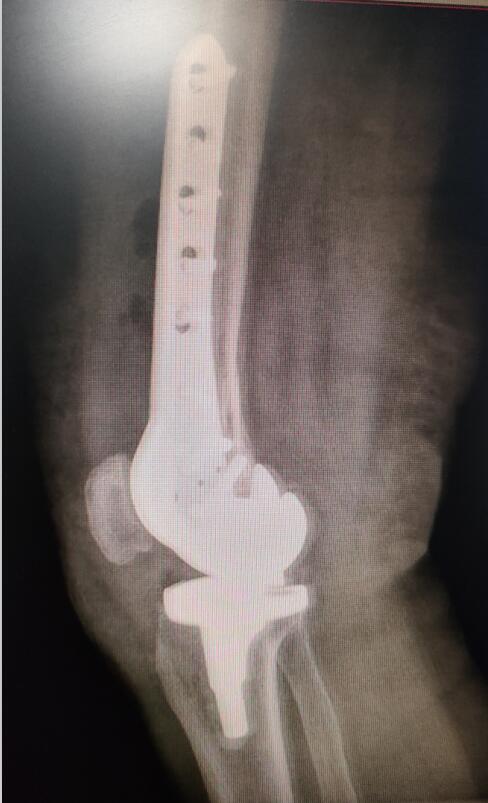

手術后照片